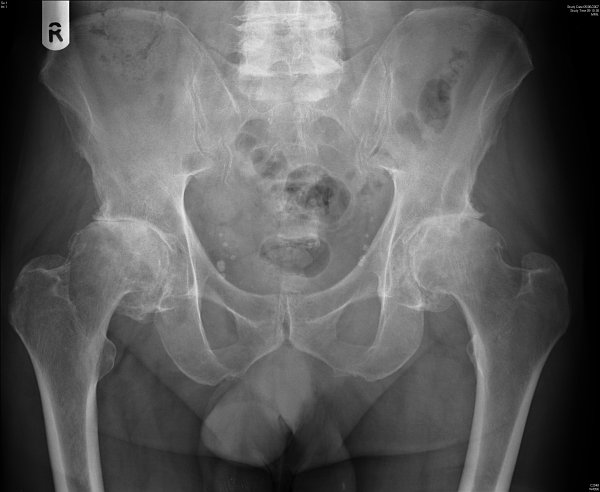

Κλινικώς διαπιστώνεται περιορισμός στις κινήσεις της άρθρωσης κυρίως της απαγωγής και έξω στροφής με αποτέλεσμα σε προχωρημένα στάδια το σκέλος να παίρνει ανώμαλη θέση χαρακτηριστική για την πάθηση, δηλαδή βρίσκεται σε κάμψη, προσαγωγή και εξωτερική στροφή. Η διάγνωση βασίζεται στην κλινική εικόνα και τον ακτινολογικό έλεγχο.

Τα κλασσικά ακτινολογικά ευρήματα που επιβεβαιώνουν την διάγνωση είναι:

- Μείωση του μεσοαρθρίου διαστήματος (δηλ. τού κενού που φαίνεται ανάμεσα στα δύο κόκκαλα)

- Σκλήρυνση του υποχονδρίου οστού – φαίνεται στις ακτινογραφίες σαν μια περιοχή πιο άσπρη απ’ ότι θα έπρεπε

- Μικρές κύστες στην περιοχή του υποχονδρίου οστού

- Οστεόφυτα στις παρυφές των αρθρικών επιφανειών